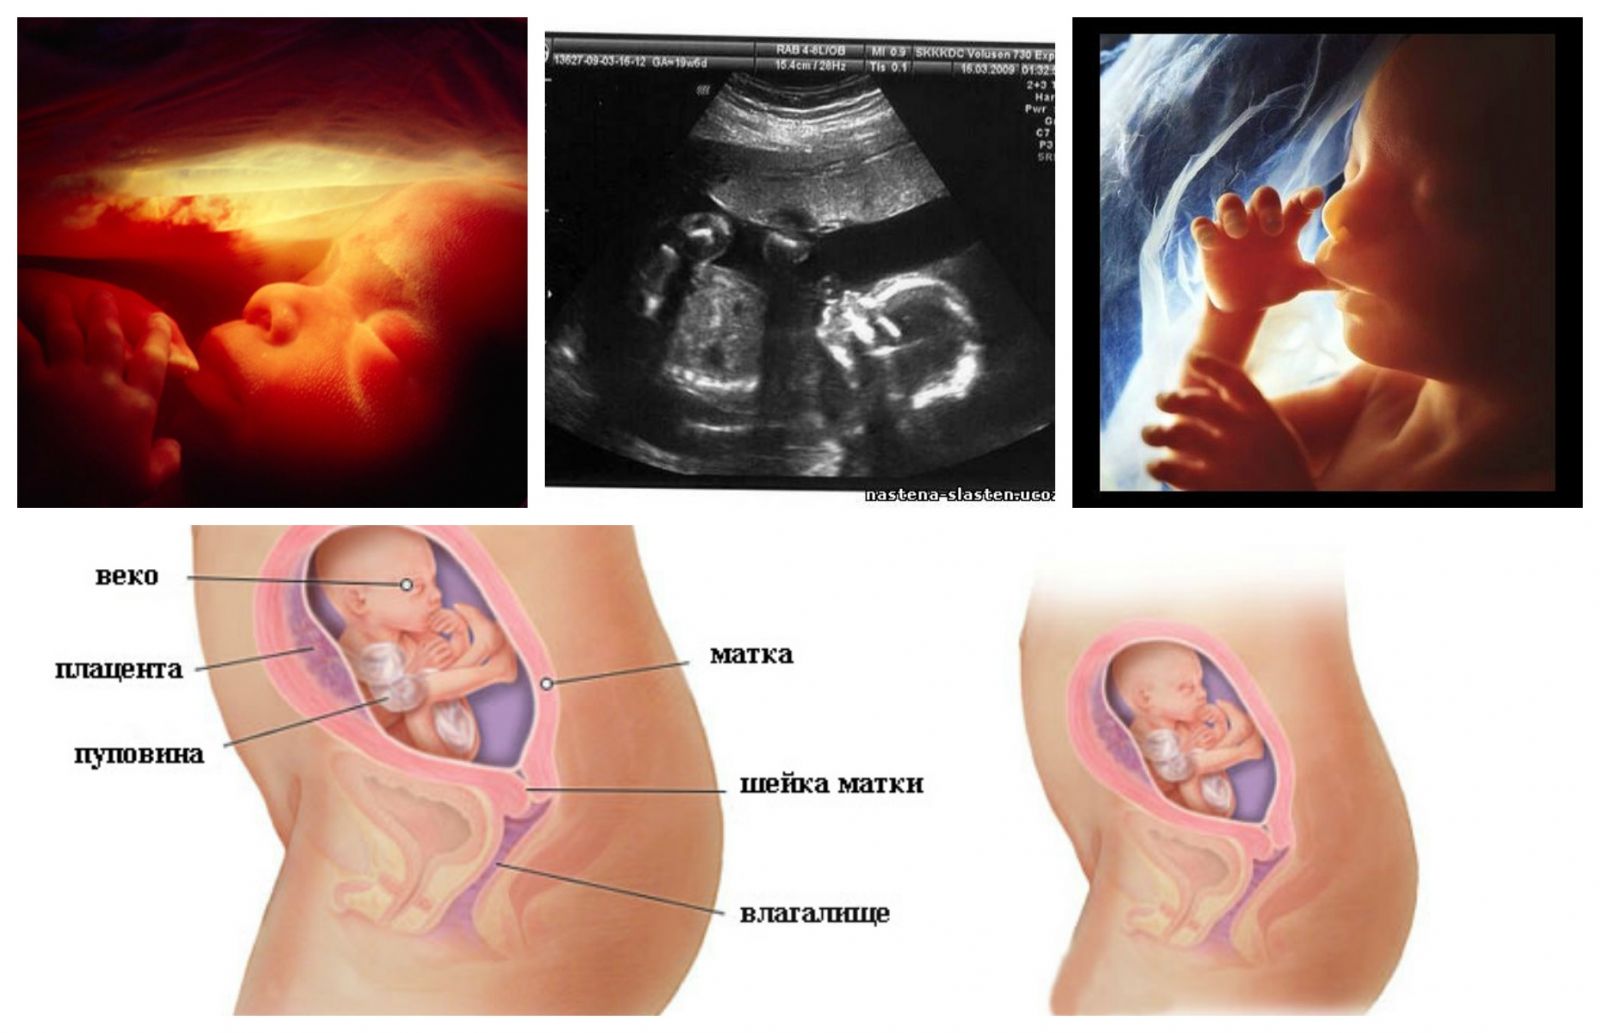

Фотография Плода В Животе

Фотография Плода В Животе 113 фотографий